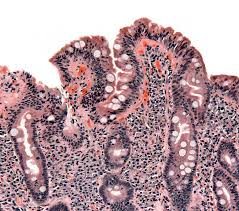

Coeliac disease is a condition where the lining of the small bowel is damaged due to a protein in food called gluten. It is an autoimmune disease. Of the signs of celiac disease listed above, anemia, delayed growth and weight loss are signs of malnutrition. This can make them foul smelling, greasy and frothy. Some people develop celiac disease as a child, others as an adult. This often begins between six months and two years of age. Celiac disease is a serious condition in which the immune system attacks the small intestine in response to eating gluten. Classic symptoms include gastrointestinal problems such as chronic diarrhoea, abdominal distention, malabsorption, loss of appetite, and among children failure to grow normally.

Coeliac disease develops in genetically susceptible individuals who, in response to unknown environmental factors, develop an immune response that is subsequently triggered by the ingestion of gluten. The reason for this is still unknown. Malabsorption can also lead to stools (poo) containing abnormally high levels of fat (steatorrhoea). Gluten is a protein found naturally in wheat, barley, and rye, and is common in foods such as bread, pasta, cookies, and cakes. This causes damage to the lining of the gut and means the body can't properly absorb nutrients from food. This often begins between six months and two years of age. Celiac disease is a serious condition in which the immune system attacks the small intestine in response to eating gluten. This damages your gut (small intestine) so you are unable to take in nutrients. 1 2 inflammation may lead to the malabsorption of several important nutrients. Gluten is a protein in wheat,. Coeliac disease is not a food allergy or a food intolerance. Coeliac disease is an inflammatory disease of the upper small intestine and results from gluten ingestion in genetically susceptible individuals. Coeliac disease is a condition where your immune system attacks your own tissues when you eat gluten.

The inflammation is triggered by eating foods that contain gluten. 1 2 inflammation may lead to the malabsorption of several important nutrients. Gluten is a protein found naturally in wheat, barley, and rye, and is common in foods such as bread, pasta, cookies, and cakes. People who experience any of the following should also be screened for coeliac disease. This causes damage to the lining of the gut and means the body can't properly absorb nutrients from food. Celiac disease is an autoimmune condition that causes severe damage to the lining of the small intestine. The main ways that coeliac disease can affect the body is: Symptoms of celiac disease vary widely, and a person may have multiple symptoms that come and go.